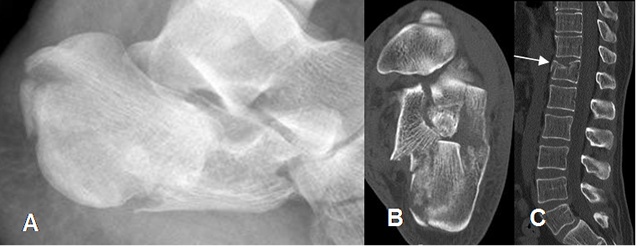

Fig 47. Fractura del calcáneo.

A: Rx lateral y B: TAC axial de calcáneo. Fractura impactada y conminuta del calcáneo, con un ángulo de Bohler negativo.

C: TAC reconstrucción lateral. Fractura asociada en el cuerpo de D12.